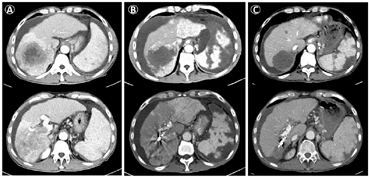

后患者规律服用索拉非尼抗肿瘤治疗,2019年7月18日入院复查发现肝左叶出现新发异常强化病灶,考虑病情进展,因为经济原因及患者拒绝介入手术治疗,靶向药物更换为瑞戈非尼,继续抗肿瘤治疗;2020年5月18日复查甲胎蛋白及糖类抗原125降至正常水平,腹部增强CT检查示肝内病灶未见明显强化,结合影像检查及实验室检查结果,mRECIST评估为完全缓解(CR),后规律复查至今,目前随访40个月。患者介入手术前后肝癌及门静脉癌栓变化见图1;从最初治疗开始,患者甲胎蛋白、糖类抗原125、白细胞计数、血小板含量变化见图2。